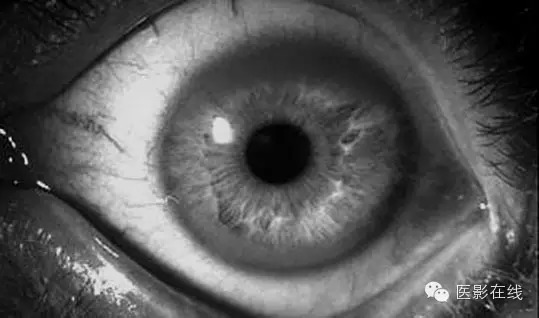

女性,8岁。患儿近1个月来,发现腹部明显增大、膨隆,起初因为无明显不适症状而未行特殊检查及治疗,近十天来,腹部增大加重。并发现巩膜及颜面皮肤黄染,偶有恶心、呕吐胃内容物。四肢无力。精神较差,无发热、抽搐、咳嗽、咳痰等症状。以黄疸待查收入院。实验室检查:尿铜增高。眼科检查:患儿有典型的K F环。颅脑CT检查未见异常。 腹部CT检查见下图。

结合病史及眼科检查:患儿有典型的K F环。支持肝豆状核变性。肝豆状核变性是以青少年为主的遗传性疾病,由铜代谢障碍引起。其特点为肝硬化、大脑基底节软化和变性、角膜色素环(Kayser Fleischer环),伴有血浆铜蓝蛋白缺少和氨基酸尿症。又名Wilson病。K F环、血铜蓝蛋白、尿铜测定是必要的诊断步骤。(zhw974247)

肝豆状核变性的诊断依据为:①眼科裂隙灯检查异常。K F环阳性。②血液生化异常。血清铜氧化酶活力下降,和(或)血清铜蓝蛋白水平下降尿铜含量增高。③典型椎体外系神经症状。④不典型肝、肾、胃肠道等症状。⑤影像学检查异常。脑CT双侧豆状核对称性低密度灶、结节性肝硬化或肝脂肪变性。⑥排除其他疾病。

本例患者肝脏呈典型的结节性肝硬化改变,虽然颅脑CT检查未发现双侧豆状核对称性低密度灶,但结合患者发病年龄小、尿铜增高、眼底K F环,还是可以确诊为肝豆状核变性的。

肝豆状核变性(Wilson 病)是先天性铜代谢障碍疾病,累及肝脏、肌肉、神经、角膜,有时全身的症状并不同时出现,只出现单个脏器损害的表现,极容易忽视而误诊。通过本病的分析,给我们启发:当临床上遇见儿童、青少年出现不明原因的黄疸,不支持病毒性肝炎,应该想到肝豆状核变性,要检查眼睛角膜有无K F环,检查颅脑有无在豆状核、尾状核,丘脑、中脑(黑质红核)、小脑齿状核以及大脑皮质和皮质下区出现低密度影像。反之,当遇见进行性肢体震颤肌强直构音困难的年轻患者,也应该检查肝脏情况和尿铜情况。全身性疾病应该从全身的角度整体分析。